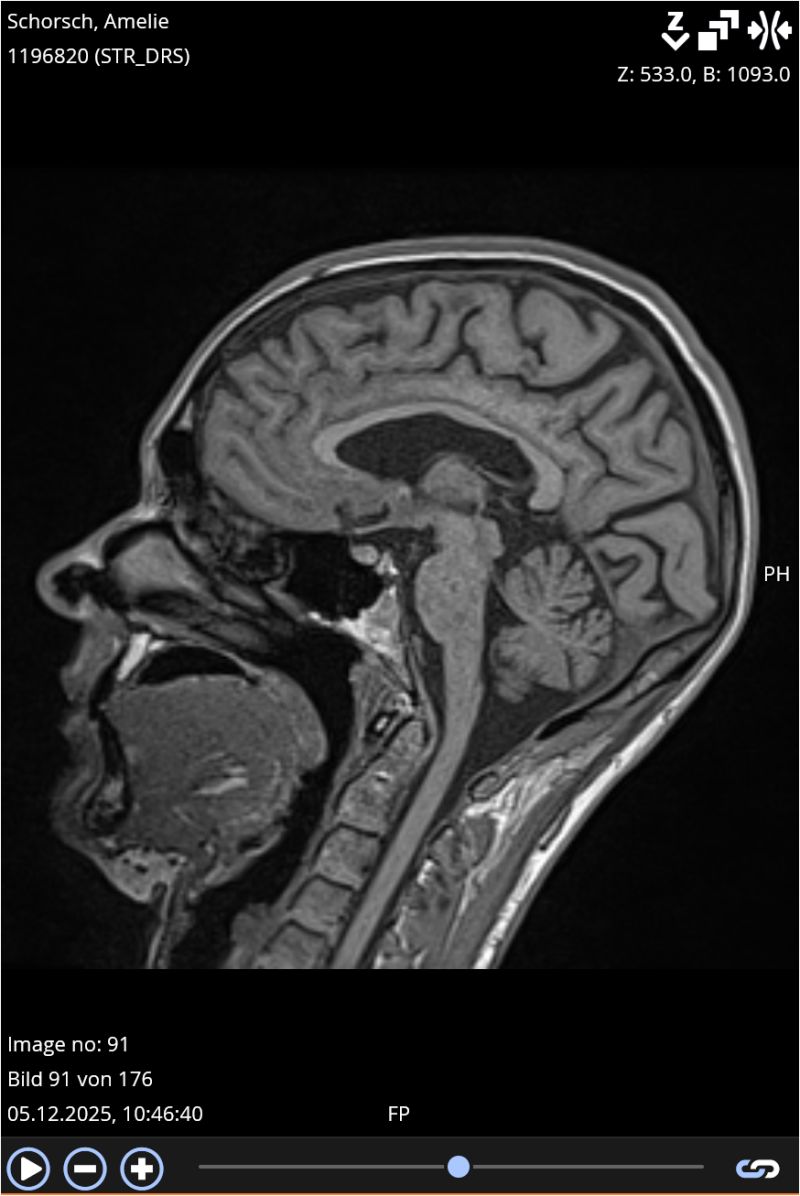

Diese Woche war ich mal wieder im MRT.

Ein Termin, der jedes Jahr ansteht.

Ein Termin, der rational „Routine“ ist – und emotional alles andere als das.

Diesmal: keine Aktivität.

In der sekundär progredienten MS (SPMS)

nimmt die klassische entzündliche Aktivität meistens ab,

man sieht seltener neue, aktiv entzündliche Läsionen, also „lodernde Feuer“.

Mein MRT war dieses Jahr ruhig.

* Das liegt daran, dass die SPMS oft durch Prozesse vorangetrieben wird, die im MRT weniger sichtbar sind, z. B. langsame axonale Schäden oder Mikroentzündungen.

Und trotzdem ist ein MRT ohne neue Aktivität ein gutes Zeichen, weil es bedeutet: Keine zusätzlichen Entzündungsherde, kein neuer akuter Schaden.